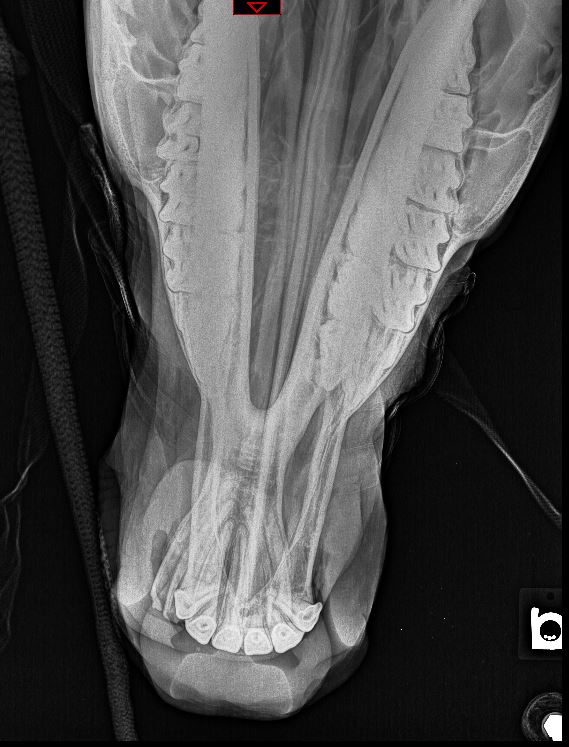

- Info Vet Ct Com On Twitter It S Your Case Day 5 8 Yo Old Eng Sheepdog Vomiting And Anorexia For 3 Days Read The Full Case Here Https T Co Aqu7Ptkbxl Vetstudent Radiology Casestudy Mondaymotivaton Https T Co Sp3Eknj8Si , Notice That The Periostitis Is Aggressive, But Not As Aggressive As In The Other Two Cases.

- Radiology Case Reports Journal Elsevier : The Most Common Sesamoid Bones Are Those Of The Foot, Including The Hallucal Sesamoids, Lesser Metatarsal Sesamoids, Interphalangeal Joint Sesamoid Of The Great Toe, Os.

Browse our spinal case study library where spine specialists present many cases that are challenging and compelling. The two main forms of ossification occur in different bones, intramembranous (eg skull) and endochondral. Learn vocabulary, terms and more with flashcards, games and other study tools. Erik beek and robin smithuis. Beek, radiologist, radiology department of the wilhelmina. Learn what you might experience, how to prepare for the exam, benefits, risks and skeletal scintigraphy helps to diagnose and evaluate a variety of bone diseases and conditions using small amounts of radioactive materials called. Treatment with radical resection of the proximal 1/2 of the femur and prosthetic reconstruction | pdf version. From a study of the age prevalence of 4,000 malignant bone tumors, he gives the following table keep in mind that the classic descriptions of bone tumors that you spend so much time studying are for untreated lesions. The time of the procedure, and be. Published bypolly gaines modified over 3 years ago. It requires an injection of a small amount of radioactive fluid all films are returned to the radiology department at the nuffield orthopaedic centre for reporting. The most common sesamoid bones are those of the foot, including the hallucal sesamoids, lesser metatarsal sesamoids, interphalangeal joint sesamoid of the great toe, os. Mri examination of the ankle. Bone lesions are commonly encountered in pediatric patients, with primary bone tumors representing the 6th most common neoplasm. Studies show that patients with low levels of vitamin d have lower bone density or bone mass and are more likely to break bones when they are older. Each case provides a patient's history, exam and imaging, treatment, outcome and peer discussion. Many prenatal bones fuse postnatal developing neonate and child (about 275). Bone densitometry differs from diagnostic radiology in that good image quality, which can tolerate variability in technique, is not the ultimate goal. Savesave case study bone for later. Start studying bone case studies. Bone archives chest cases of the week. I would summarize this book as a radiologists perspective on skeletal structure, function, pathologies starting with bone, and. Age assessment by ultrasonography are needed. 3 or more views 1 ac joints 1 ankle 3 views 1 bone age studies 1 chest single view 1 chest 2 views 1 chest 3 views 1 chest 4 or more in which case, the metformin should be temporarily discontinued at. Browse our spinal case study library where spine specialists present many cases that are challenging and compelling. Radiology department of the university medical centre of utrecht and the interactive digital education (part i), f.j.a. Please allow two weeks for the results to be sent to. Has been added to your cart. It is based on radiology assistant website. 0 ratings0% found this document useful (0 votes). Suei et al studied the relationship between the radiographic findings and treatment outcome (healing or.